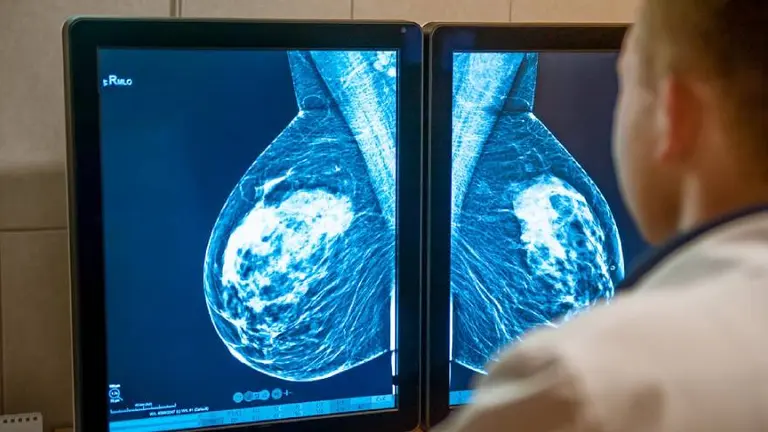

El cáncer de mama que se detecta temprano, cuando el tumor es pequeño y no se ha extendido, es más fácil de tratar con buenos resultados. Sin embargo, en los últimos años, los grandes avances de la ciencia en este campo vienen dándose para mejorar el pronóstico de los casos de cáncer de mama metastásico, aquellos en los que el tumor se ha propagado hacia otras áreas del cuerpo, como los pulmones, ganglios linfáticos distantes, la piel, los huesos, el hígado o el cerebro. En este sentido, acaban de difundirse las conclusiones de una investigación que demostró los resultados más contundentes de la historia del cáncer de mama metastásico en términos de prolongación de la vida de las pacientes.

Durante el Congreso Anual de la Sociedad Europea de Oncología Clínica (ESMO por su sigla en inglés), que está llevándose adelante del 16 al 21 de este mes, se anunciaron los resultados del estudio en fase 3 denominado MONALEESA-2, que evaluó los beneficios de ribociclib, en combinación con letrozol, versus placebo más letrozol, como primera línea de tratamiento en mujeres postmenopáusicas con un subtipo muy frecuente de cáncer de mama, conocido como RH+ HER2- (que responde a terapia hormonal y que no sobreexpresa la proteína HER2), en estadio metastásico.